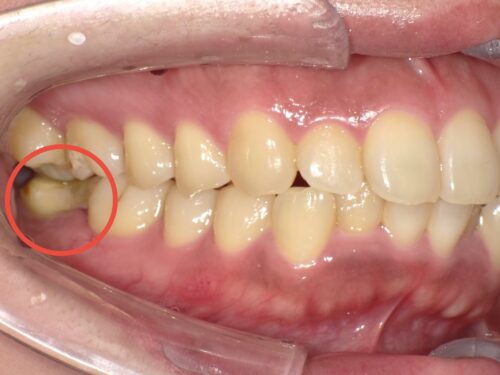

割れてしまった奥歯です。

歯が真ん中から割れており、痛みを生じていました。

レントゲン写真を見ると、以前根管治療を受けて失活歯(神経が死んでいる歯)となっていたことがわかりました。

赤い円で示しているところです。この歯が破折してしまいました。